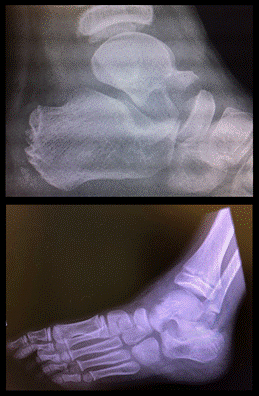

Destacamos la presencia del signo de Hawkins positivo en el control imagenológico a los 3 meses luego de la lesión, siendo este un elemento que nos indica preservación de la vascularización del astrágalo.

Del control a los 3 años luego de la intervención quirúrgica se destaca una excelente evolución clínica. Se realizó la escala AOFAS, con previo consentimiento de los padres, obteniendo una puntuación de 93/100. No presentó limitaciones en cuanto al dolor, con un total de 40 puntos, no mostró limitaciones en cuanto a la función, con un total de 45 puntos. Observamos una leve desaxación en valgo del retropie, asintomático, con un total de 8 puntos.